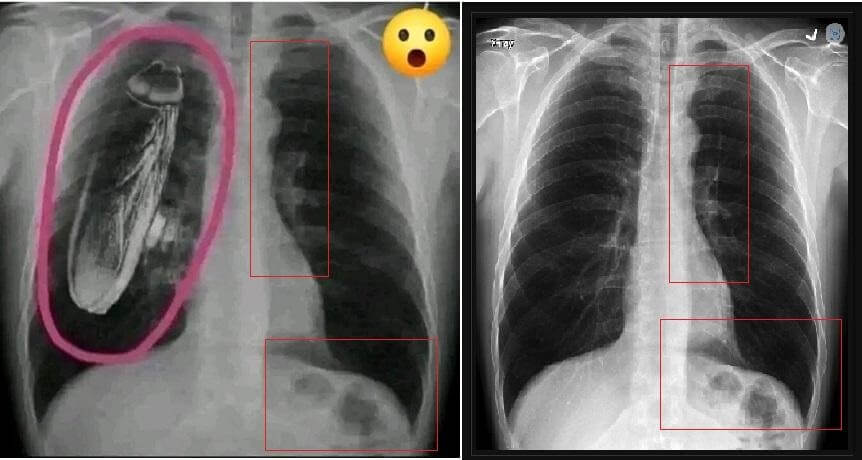

Kenya’daki bir devlet hastanesinde çekilen röntgende hastanın göğsünde canlı bir hamamböceği olduğunun sanıldığı, Singapur’da hastaya hamamböceğinin göğsünde değil, röntgen makinesinin içinde olduğunun söylendiği iddiasıyla paylaşılan görsel, orijinal değil, dijital müdahale içeriyor.

Radiopedia adlı internet sitesinde yayımlanan orijinal röntgen filmi görseli üzerine dijital ortamda (penise benzeyen) hamamböceği görseli eklenmiş.

2017 yılında aynı iddiayla kullanılan hamamböcekli röntgen filmi de dijital manipülasyon içeriyordu. Söz konusu görsel, 1954 yılında, Marilyn Monroe’nun endometriozis şikayetiyle Cedars of Lebanon Hastanesi’nde çektirdiği ve daha sonraki yıllarda açık artırmalarda yüksek meblağlara satılan göğüs röntgeni üzerine hamamböceği ekleme yapılarak oluşturulmuş (Orijinal röntgen ile viral görsel karşılaştırıldığında, kaburga kemiklerinin yapısı, omurganın duruşu ve göğüs kafesinin genel hatlarının birebir örtüştüğü, sadece hamamböceği siluetinin sonradan eklendiği net bir şekilde görülmektedir.).